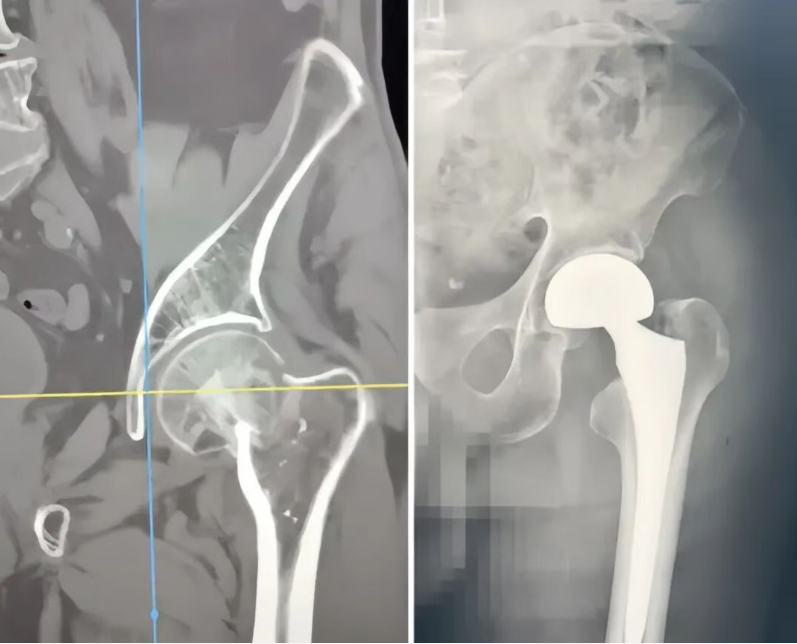

“现在能正常走路,生活能基本自理,太感谢你们了!”近日,达州市第三人民医院骨科一病区对一位88岁股骨颈骨折患者进行术后一月电话回访时,听到家属传来的好消息,医护人员感到十分欣慰,。 该患者因摔倒致左股骨颈骨折,且伴有双肺弥漫结节、肺气肿等较严重心肺基础疾病。起初,家属因手术风险极高,一度打算放弃手术——若不手术,患者将长期卧床,不仅生活质量尽失,肺炎、褥疮等并发症更会严重威胁生命;可手术的话,高龄叠加基础疾病,术中、术后的生命危险让手术成了“险棋”,对医生是一个巨大考验。 怀着“患者最大获益”的医者仁心,经过反复研究和权衡,医院骨科团队决定与家属携手,为老人争取更好的康复机会。通过向家属详细讲解手术必要性、团队保障措施后,家属被李述斌医生的专业与担当打动,给予了充分信任和支持。 手术中,手术麻醉科团队为患者实施精准麻醉,确保手术侧麻醉效果良好,为手术安全筑牢关键基础;手术麻醉科与骨科团队全程紧密配合,顺利为患者开展双极股骨头置换术。 令人欣喜的是,手术十分顺利,术后第一天患者便能下地行走。摆脱长期卧床后,患者肺部及其他基础疾病也随之改善,不久便顺利出院。术后一个月电话回访时,家属欣喜告知:患者已能正常行走,生活基本自理。 (患者家属拍摄) “患者的信任是医生永远的动力,必要的‘险’值得冒,因为最终受益者是患者。”医院骨科一病区主任医师李述斌说道。这场医患携手的“冒险”,既见证了医者的责任与担当,也离不开手术麻醉科、中医科、呼吸与危重症医学科、心血管内科的协作付出,更因医患间的信任,为高龄患者的生命与生活质量,开辟出希望之光。 专家介绍

上一篇:达州全市“惠民帮困助学”活动资助近900名贫困学子